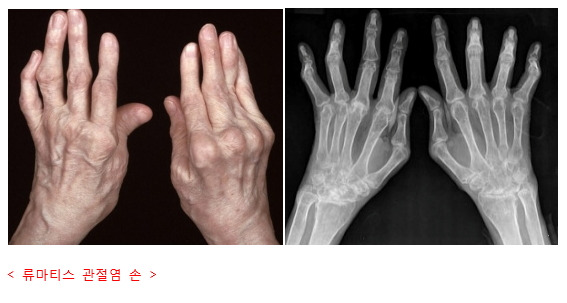

류마티스관절염은 손가락, 손목, 발가락처럼 작은 관절에서 시작되는 경우가 많으며, 염증이 만성적으로 지속되면 관절이 변형될 수 있습니다.

일반적인 퇴행성 관절염이 나이와 사용량 때문이라면, 류마티스관절염은 면역계의 오작동이 원인이라는 점에서 차이가 있습니다.